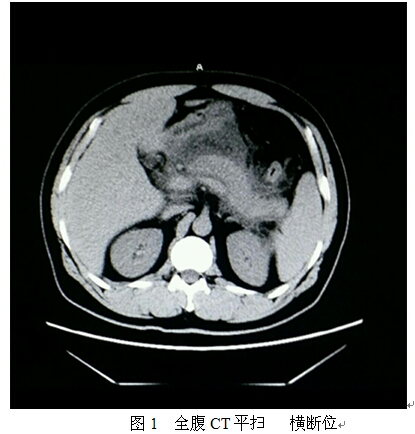

2.影像学检查:全腹部CT平扫现实:胰腺饱满、增大,边缘毛糙、不清,与周围组织分界欠清,胰腺周围可见液体密度影。其余脏器未见明显异常,腹腔内未见明显积液征像(如图1-3)。诊断为:急性胰腺炎可能性大。